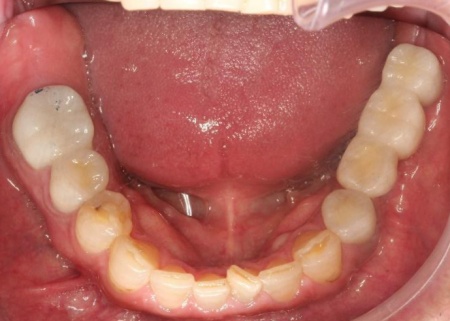

治療後

他院で治療を行った左下奥歯3本のインプラントは、土台をそのまま活かして人工歯だけ作り直し、噛み合わせを調整します。

左下奥歯1本、右下奥歯2本に装着されていた古い被せ物はすべて外し、ジルコニアクラウンと交換しました。